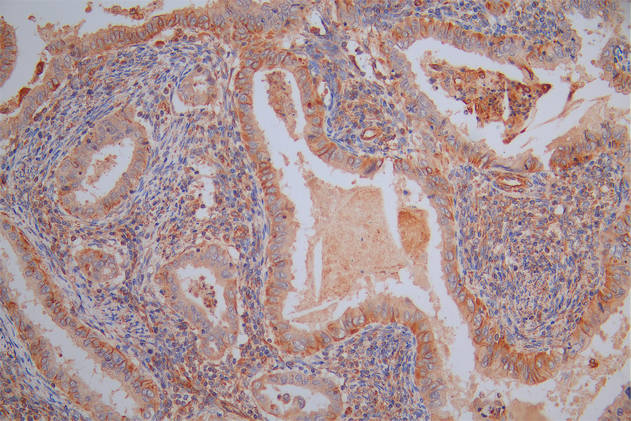

圖片: